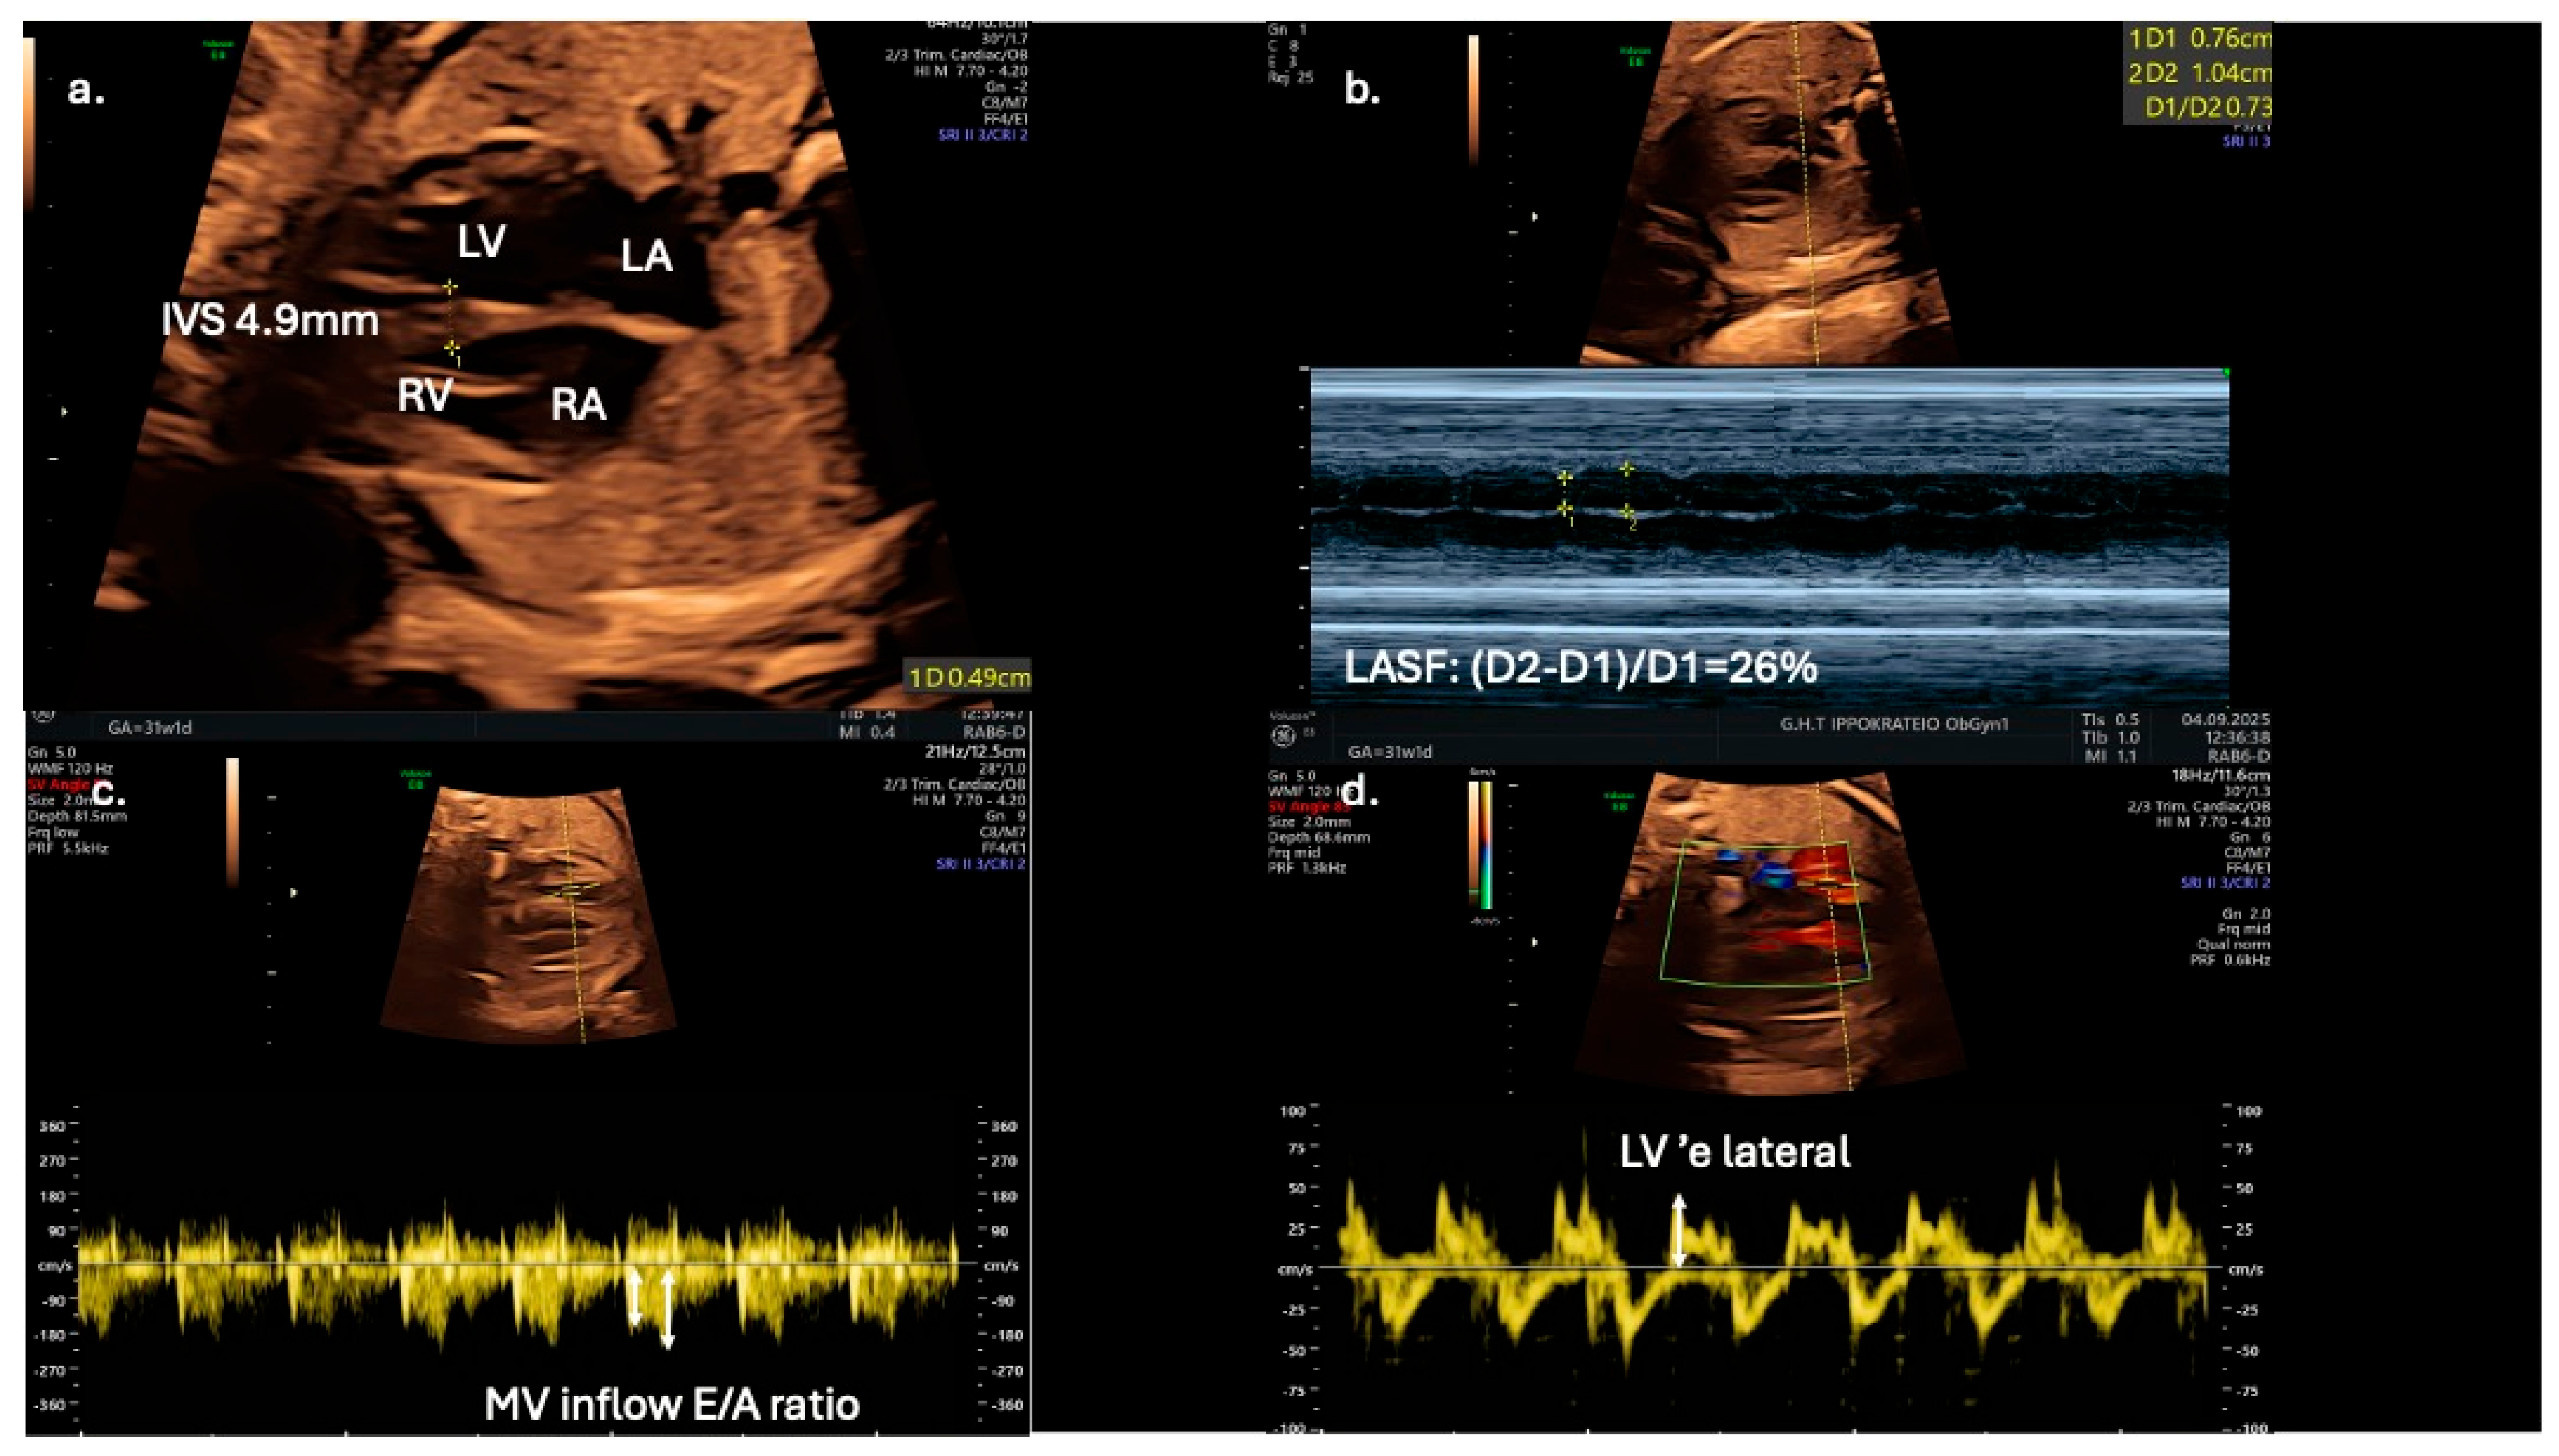

From a clinical perspective, fetal echocardiography may serve as an adjunct tool for predicting neonatal metabolic complications. Fetal IVS hypertrophy demonstrates a strong association with increased risk of neonatal hypoglycemia, hyperbilirubinemia, prolonged admissions to intensive care units, and persistent fetal shunts (e.g., patent ductus arteriosus and patent foramen ovale). However, fetal cardiac dysfunction, as evaluated by Doppler and TDI, does not reliably predict adverse perinatal events such as intrapartum fetal distress or perinatal asphyxia [13]. Speckle-tracking echocardiography is showcased as a more sensitive tool for detecting subtle fetal cardiac dysfunction, and its assessment should be considered for all fetuses of mothers with diabetes, even in the absence of septal hypertrophy, which may appear later as a less sensitive marker (Figure 3).

Figure 3.

Echocardiographic indices in a 31-gestational-week fetus of a diabetic mother; (a) interventricular septal thickness (IVS) measured in the four-chamber view; (b) in the same view, left atrial systolic shortening (LASF) is calculated using M-mode echocardiography; (c) use of pulse wave Doppler imaging in mitral inflow to calculate E/A ratio; (d) application of tissue Doppler imaging in the lateral wall of the left ventricle enables further assessment of diastolic function by calculating ‘e wave and E/’e ratio.

Early detection of diastolic dysfunction could also have significant implications for postnatal cardiovascular health [9]. Left atrial shortening fraction could serve as an adjunct novel echocardiographic parameter for evaluating diastolic function in fetuses of diabetic mothers and may improve prenatal cardiac monitoring and management (Figure 3). In addition, Mod-MPI and E/A ratio could be utilized as early biomarkers of distress, as they are possibly more sensitive than conventional tools, such as cardiotocography and umbilical artery Doppler velocimetry. for predicting adverse perinatal outcomes in gestational diabetic pregnancies. The suggested high sensitivity and specificity thresholds (100% and 92%, respectively) for Mod-MPI ≥ 0.52 shown by Bhorat I.E. et al. highlight the need for further validation of its potential clinical utility in risk stratification and surveillance protocols [12].